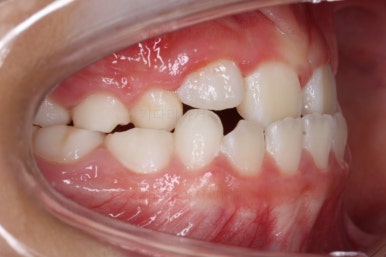

치료 시작 3개월째의 모습입니다.

윗니가 점점 앞으로 나오는게 보이실거에요. 사실은 치아가 나오는 것이 아니라 치아가 담겨있는 위턱뼈가 통째로 앞으로 나온 것입니다.

좀 더 하면 마무리를 할 수 있을 것 같네요.